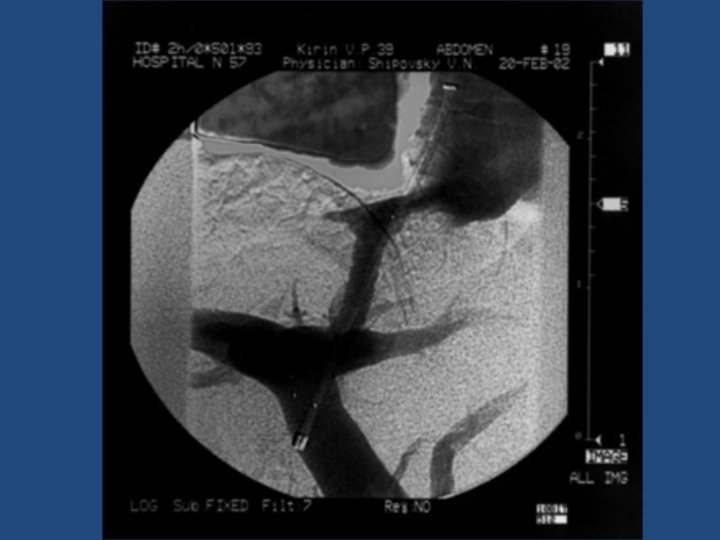

Результаты TIPS • • • Длительность процедуры 1 час до 3, 5 часов Повторные кровотечения – 10% Стеноз стента в течение двух лет – 20% Печеночная энцефалопатия Летальность 20% Максимальный срок наблюдения = 5 лет

Методика дистанционного обследования после TIPS • Клинический осмотр и лабораторные анализы • ЭГДС • Ультразвуковое дуплексное исследование портального кровотока • Ангиография ?